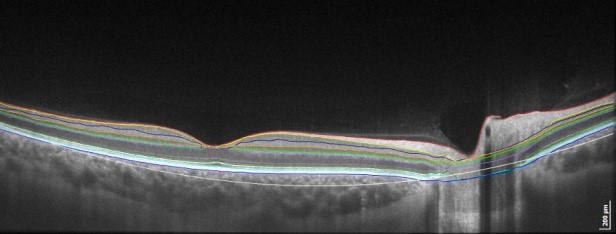

- Прибор автоматически идентифицирует 8 слоев сетчатки.

Скан широкого поля обзора

Центрированное сканирование широкого поля обзора 12х12мм – это наилучший способ диагностики сетчатки пациента. Полноценное сканирование в томограммах с большим разрешением позволяет обнаружить практически все нежелательные трансформации на начальных стадиях. Периферийное сканирование дает возможность обнаружить болезни дальней периферии.

Одно отсканированное изображение макулы в 3D позволяет провести диагностику сетчатки и глаукомы. ПО в автоматическом режиме различает 8 слоев сетчатки, это необходимо для качественного исследования и формирования диаграммы изменений в здоровье больного человека. Наличие совершенно разных методик обработки результатов и презентации дает возможность отдать предпочтение наиболее действенной для пациента, увеличивая эффективность работы.